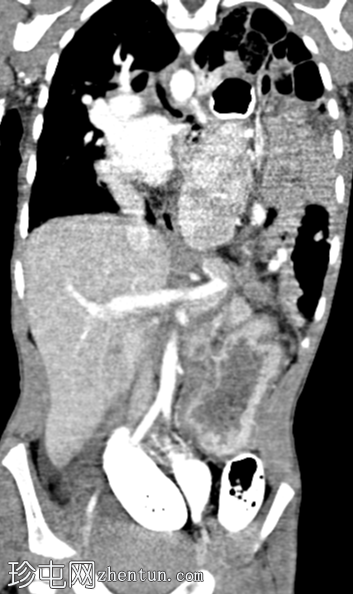

斜位

消化道造影检查显示食管口径正常,胃明显延长,延伸至盆腔区域。

左胸腔可见囊性透亮区,与腹部相连,导致心脏轮廓向右侧移位。